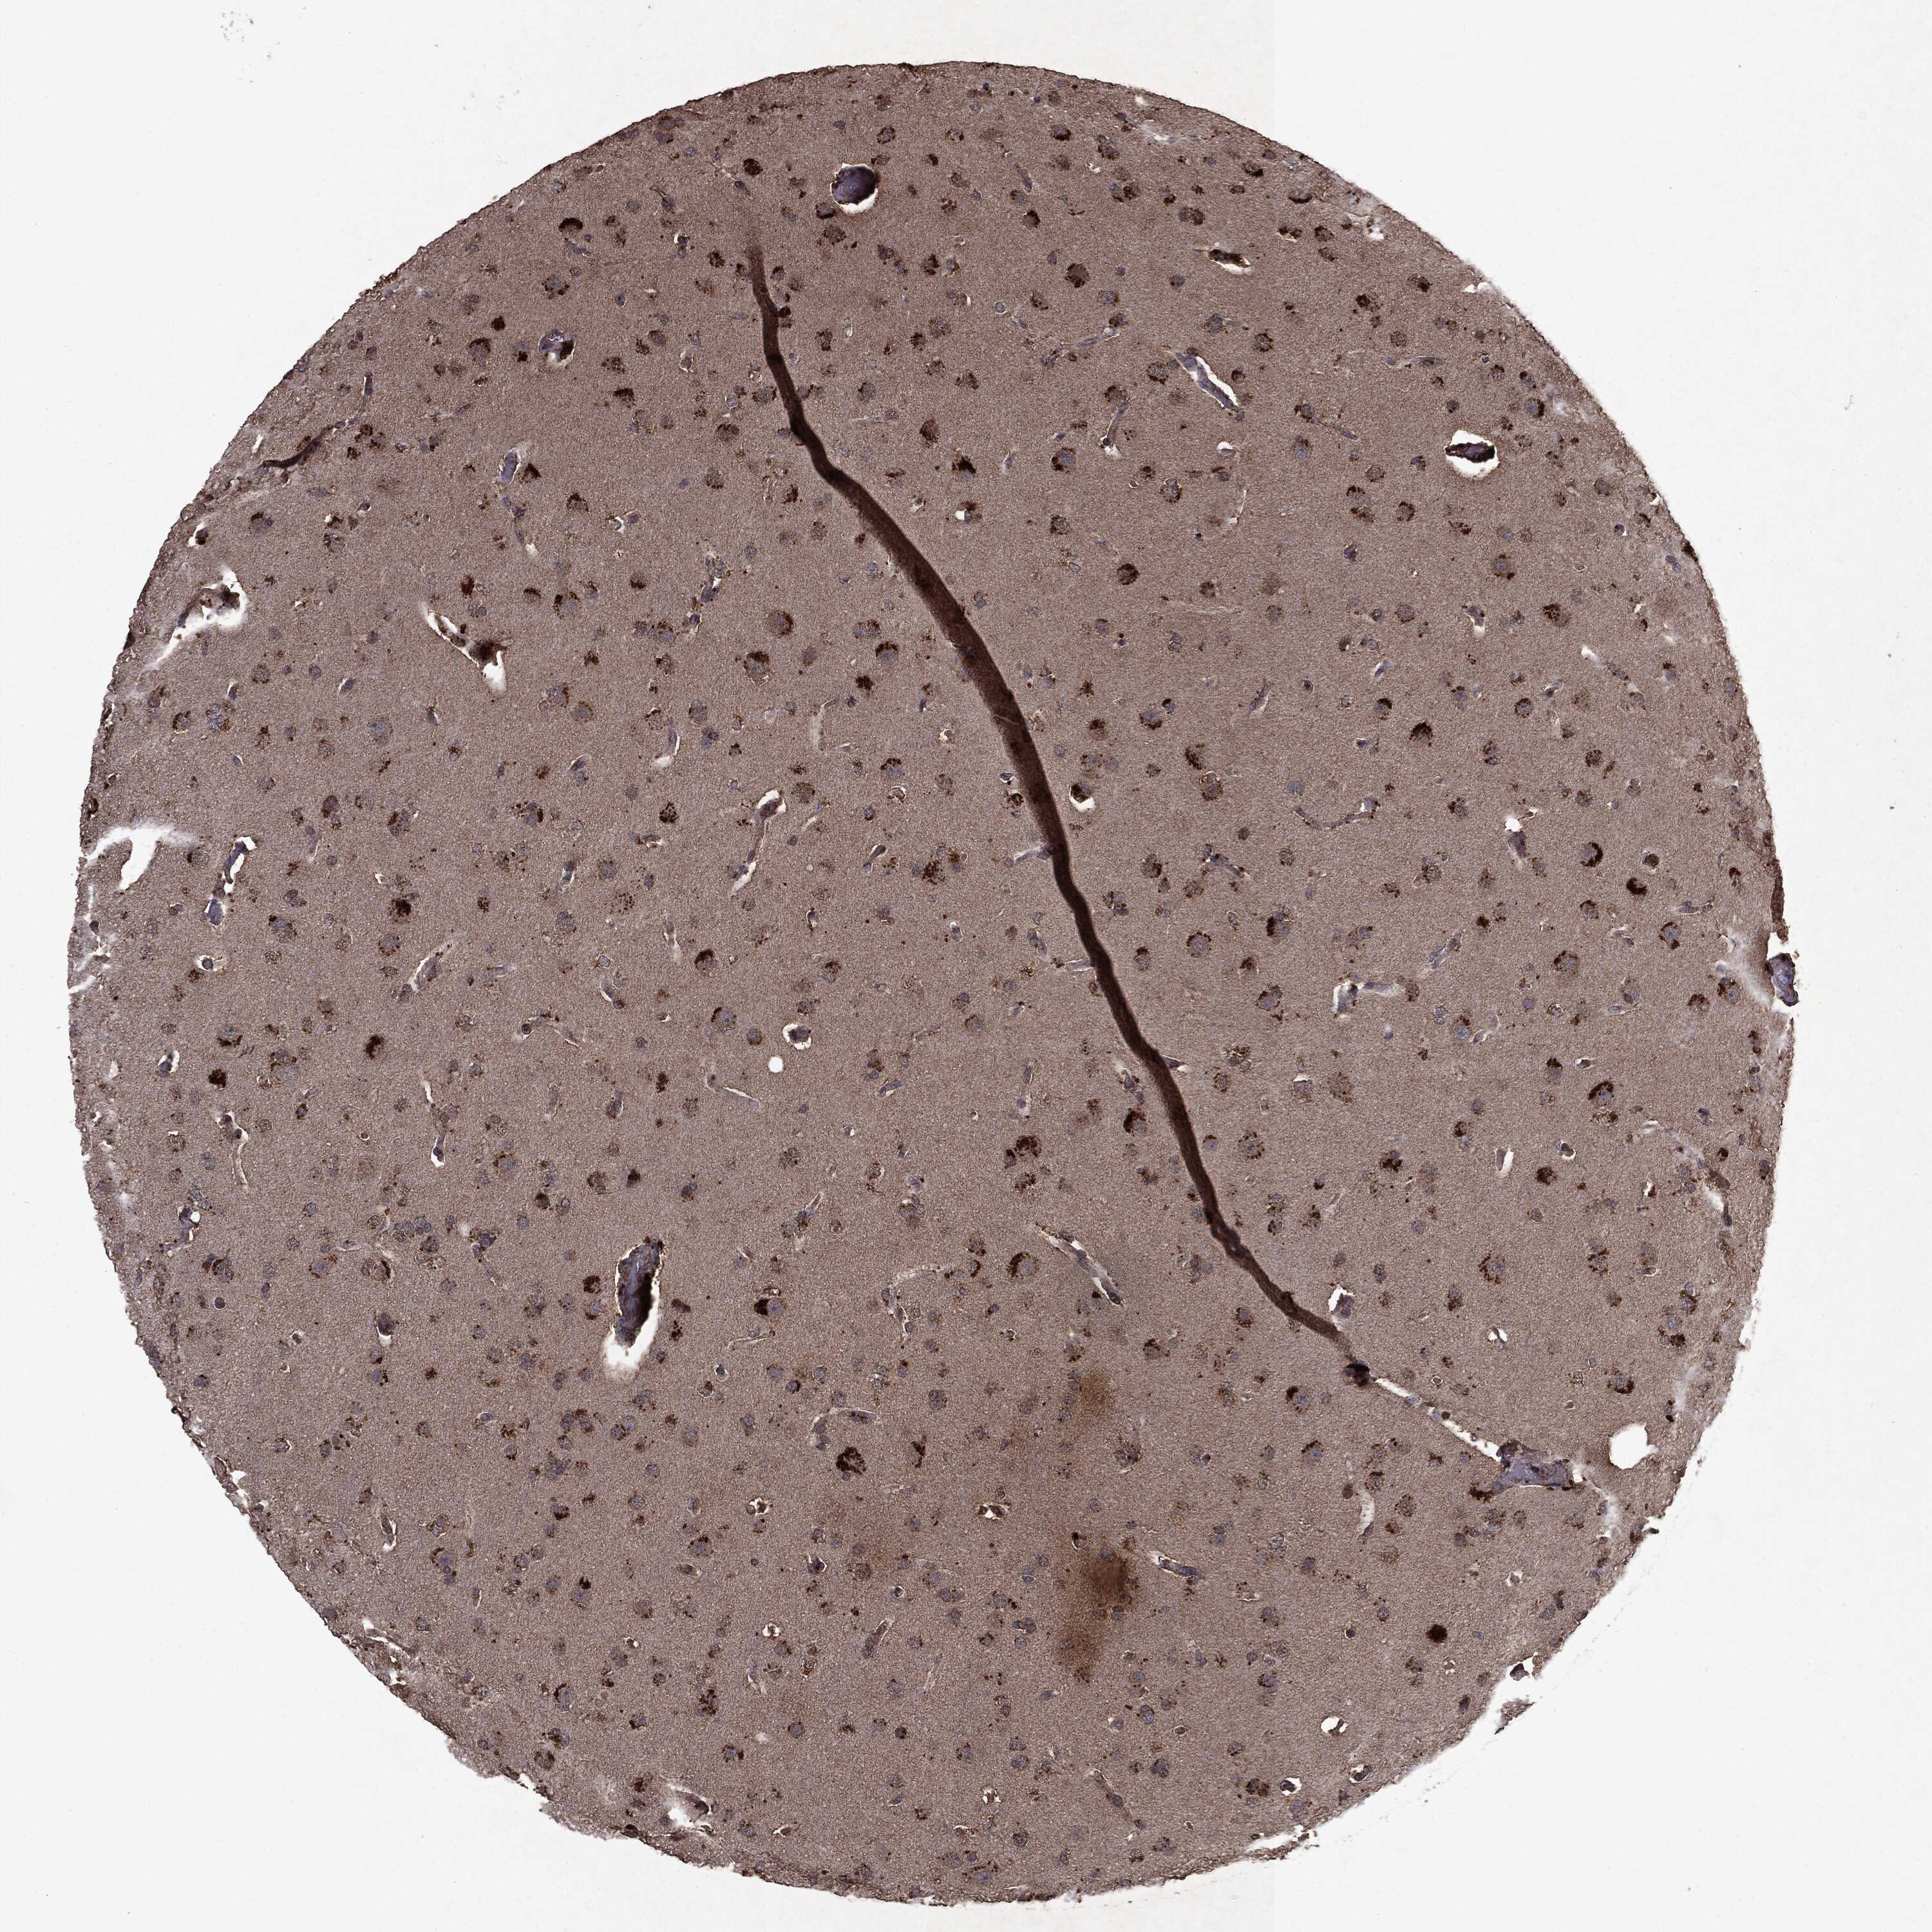

GLIOMA - Protein expressioni

A mouse-over function shows sample information and annotation data. Click on an image to view it in a full screen mode. Samples can be filtered based on level of antibody staining by selecting one or several of the following categories: high, medium, low and not detected. The assay and annotation is described here.

Note that samples used for immunohistochemistry by the Human Protein Atlas do not correspond to samples in the TCGA dataset.

Antibody stainingi

Antibody staining in the annotated cell types in the current human tissue is reported as not detected, low, medium, or high, based on conventional immunohistochemistry profiling in selected tissues. This score is based on the combination of the staining intensity and fraction of stained cells.

Each image is clickable and will lead to virtual microscopy that enables deeper exploration of all samples and also displays staining intensity scores, fraction scores and subcellular localization as well as patient and tissue information for each sample.

CAB069425

CAB080053

CAB080065

CAB080070

CAB080081

CAB080095

CAB080097

Staining

High

Medium

Low

Not detected

Intensity

Strong

Moderate

Weak

Negative

Quantity

>75%

75%-25%

<25%

None

Location

Nuclear

Cytoplasmic/membranous

Cytoplasmic/membranous,nuclear

Glioma, malignant, Low grade

Glioma, malignant, High grade

Glioma, malignant, NOS